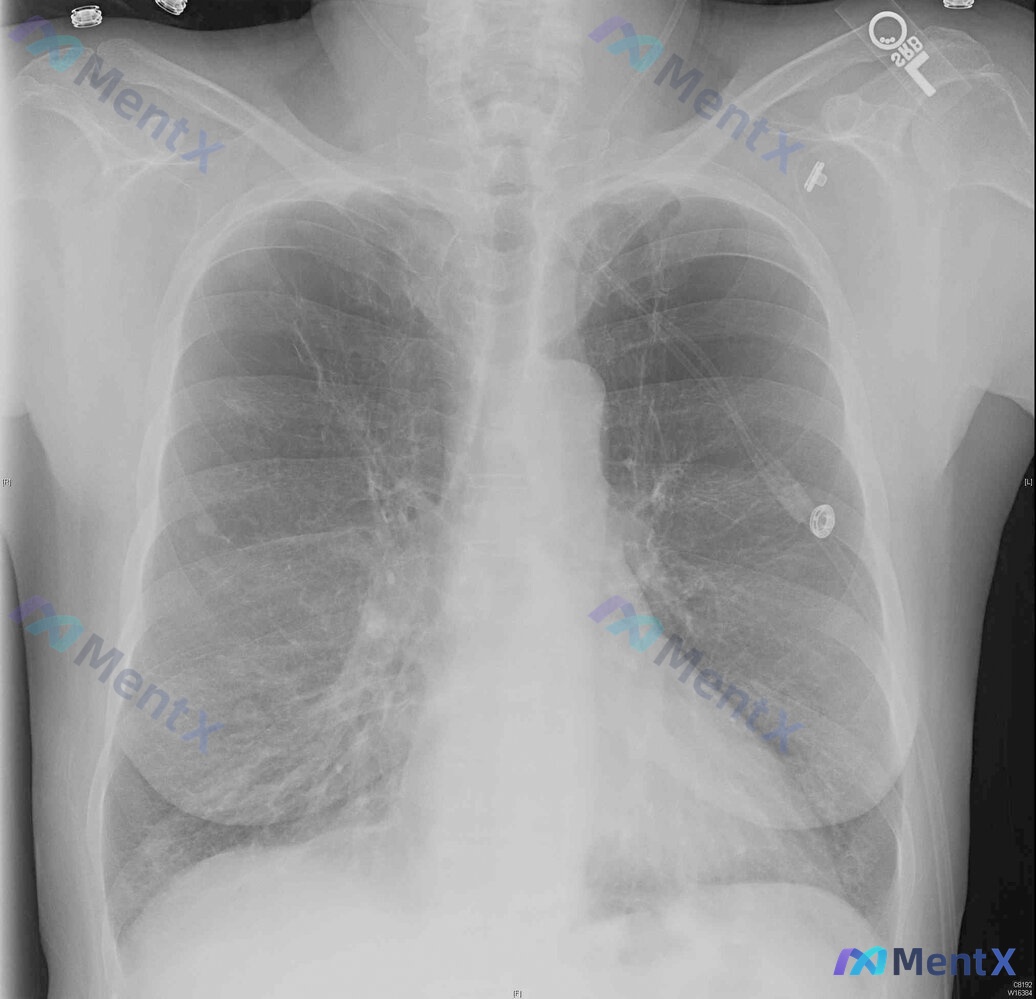

85岁女性呼吸困难12小时,胸片却完全正常,下一步最该做什么?

整理到一个挺有警示意义的病例: 85岁女性,长期居住在固定护理机构,因12小时呼吸困难被救护车送急诊。 初始生命体征与一般情况: - 心率140次/分,呼吸29次/分 - 未吸氧时SpO2 72%,予100%氧气(非重复呼吸面罩)后纠正为86% - 难以唤醒,有短暂的胸膜刺激性发作 - 无预先指示,...